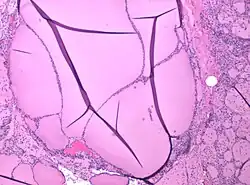

Colloid nodules are distinguished by an apparently gelatinous mass of colloid both surrounding and contained within follicular cells. Colloid nodules are not surrounded by a fibrous capsule of compressed tissue. However, they are surrounded by flattened epithelial cells.[8] Both the number of cells and the type of colloid may vary considerably.[7]